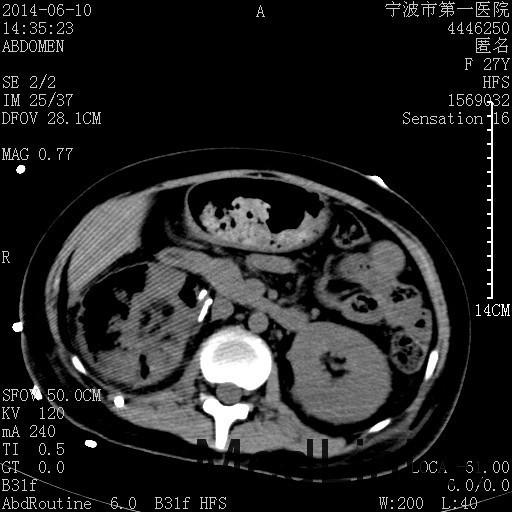

患者,女,27岁,因“右下腹疼痛伴呕吐2天”入院 患者无明显诱因出现右下腹疼痛伴呕吐、发热,体温最高39度,急诊CT示:右肾集气,考虑气性肾盂肾炎。

查体: 右肾区叩击痛,右下腹压痛,无反跳痛。 辅助检查: 空腹血糖9.7mmo/L,餐后血糖18mmol/L 血常规:白细胞 11.3*109/L, 中性百分比 77.4%, 血红蛋白 8g/L, 血小板 319*109/L 尿常规 WBC+++ 生化:白蛋白 37.5g/L,肝肾功能正常 泌尿系CT:右肾集气

诊断为“气性肾盂肾炎,感染性休克,糖尿病酮症酸中毒” 血、尿、脓液培养均示“克雷伯杆菌” 入院第2天行“右双J管置入术” 入院第3天、7天行“右肾穿刺造瘘术” 入院1月行“右肾切除术” 术后顺利康复出院。